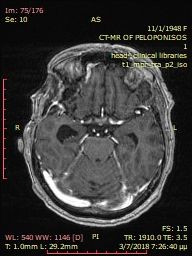

Example 1

Pre-operative brain meningioma